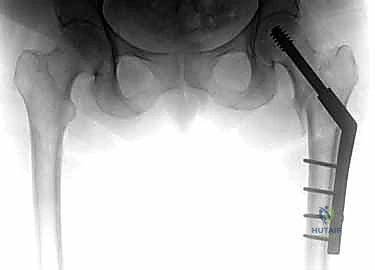

| وجه المقارنة | الشريحة والمسمار المنزلق (DHS - Dynamic Hip Screw) | المسمار النخاعي القريب (PFN - Proximal Femoral Nail) |

|---|---|---|

| آلية العمل | شريحة معدنية تُثبت على السطح الخارجي للعظم مع مسمار كبير يخترق عنق الفخذ. | مسمار من التيتانيوم يُدخل داخل التجويف النخاعي للعظم (من الأعلى) مع مسامير عرضية للتثبيت. |

| نوع الكسور المناسبة | الكسور المستقرة (Stable Fractures) ذات التفتت البسيط. | الكسور غير المستقرة (Unstable)، المفتتة بشدة، أو التي تمتد لأسفل العظم. |

| الشق الجراحي | شق جراحي جانبي أطول نسبياً (حوالي 10-15 سم). | جراحة طفيفة التوغل، شقوق صغيرة جداً (Minimally Invasive). |

| الميكانيكا الحيوية | يوفر ضغطاً ديناميكياً ممتازاً على موقع الكسر أثناء المشي. | يوفر دعماً ميكانيكياً أقوى لأنه يقع في مركز ثقل العظم (محور تحمل الوزن). |

| فقدان الدم | أكثر نسبياً مقارنة بالمسمار النخاعي. | أقل بكثير. |

| سرعة التعافي | ممتازة، ولكن قد تتطلب حذراً أكبر في الكسور غير المستقرة. | أسرع، ويسمح بتحميل الوزن في وقت أبكر في الحالات المعقدة. |

مجموعة من الصور الإضافية التي توضح مراحل دقيقة من العمل الجراحي المعقد الذي يجريه الأستاذ الدكتور محمد هطيف لضمان أعلى درجات الدقة الميكانيكية الحيوية: